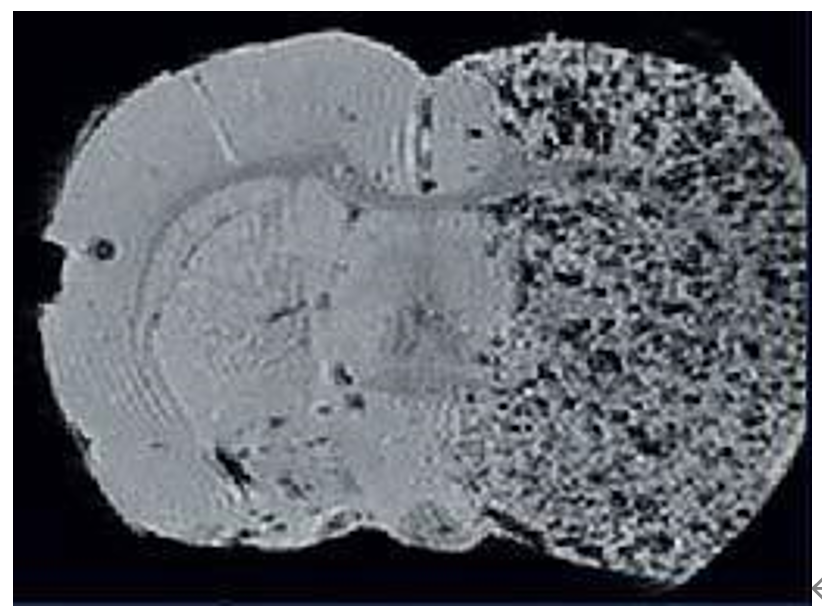

8、分子影像成像

分子磁共振成像是是一個(gè)新興并具有很大發(fā)展前景的領(lǐng)域。隨著布魯克獨(dú)特的低溫探頭技術(shù)進(jìn)入磁共振成像領(lǐng)域,磁共振圖像的空間分辨 率達(dá)到一個(gè)新的層次。這些特有的提高靈敏度技術(shù)結(jié)合布魯克超高場(chǎng) 強(qiáng)磁體,使磁共振成像進(jìn)入細(xì)胞水平。

利用標(biāo)記Fe的間質(zhì)干細(xì)胞來(lái)顯示大鼠中風(fēng)區(qū)域: